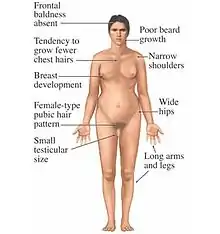

Some of the most frequent genetic disorders are abnormalities of sex chromosomes, but polysomies rarely occur.[18] 49,XXXXY chromosome polysomy occurs every 1 in 85,000 newborn males.[19] The incidence of other X polysomies (48,XXXX, 48,XXXY, 48,XXYY) is more rare than 49,XXXXY.[20] Polysomy Y (47,XYY; 48,XYYY; 48,XXYY; 49,XXYYY) occurs in 1 out of 975 males and may cause psychiatric, social, and somatic abnormalities.[21] Polysomy X may cause mental and developmental retardation and physical malformation. Klinefelter syndrome is an example of human polysomy X with the karyotype 47, XXY. X chromosome polysomies can be inherited from either a single maternal (49, X polysomies) or paternal (48, X polysomies) X chromosome.[18] Polysomy of sex chromosomes is caused by successive nondisjunctions in meiosis I and II.[6]